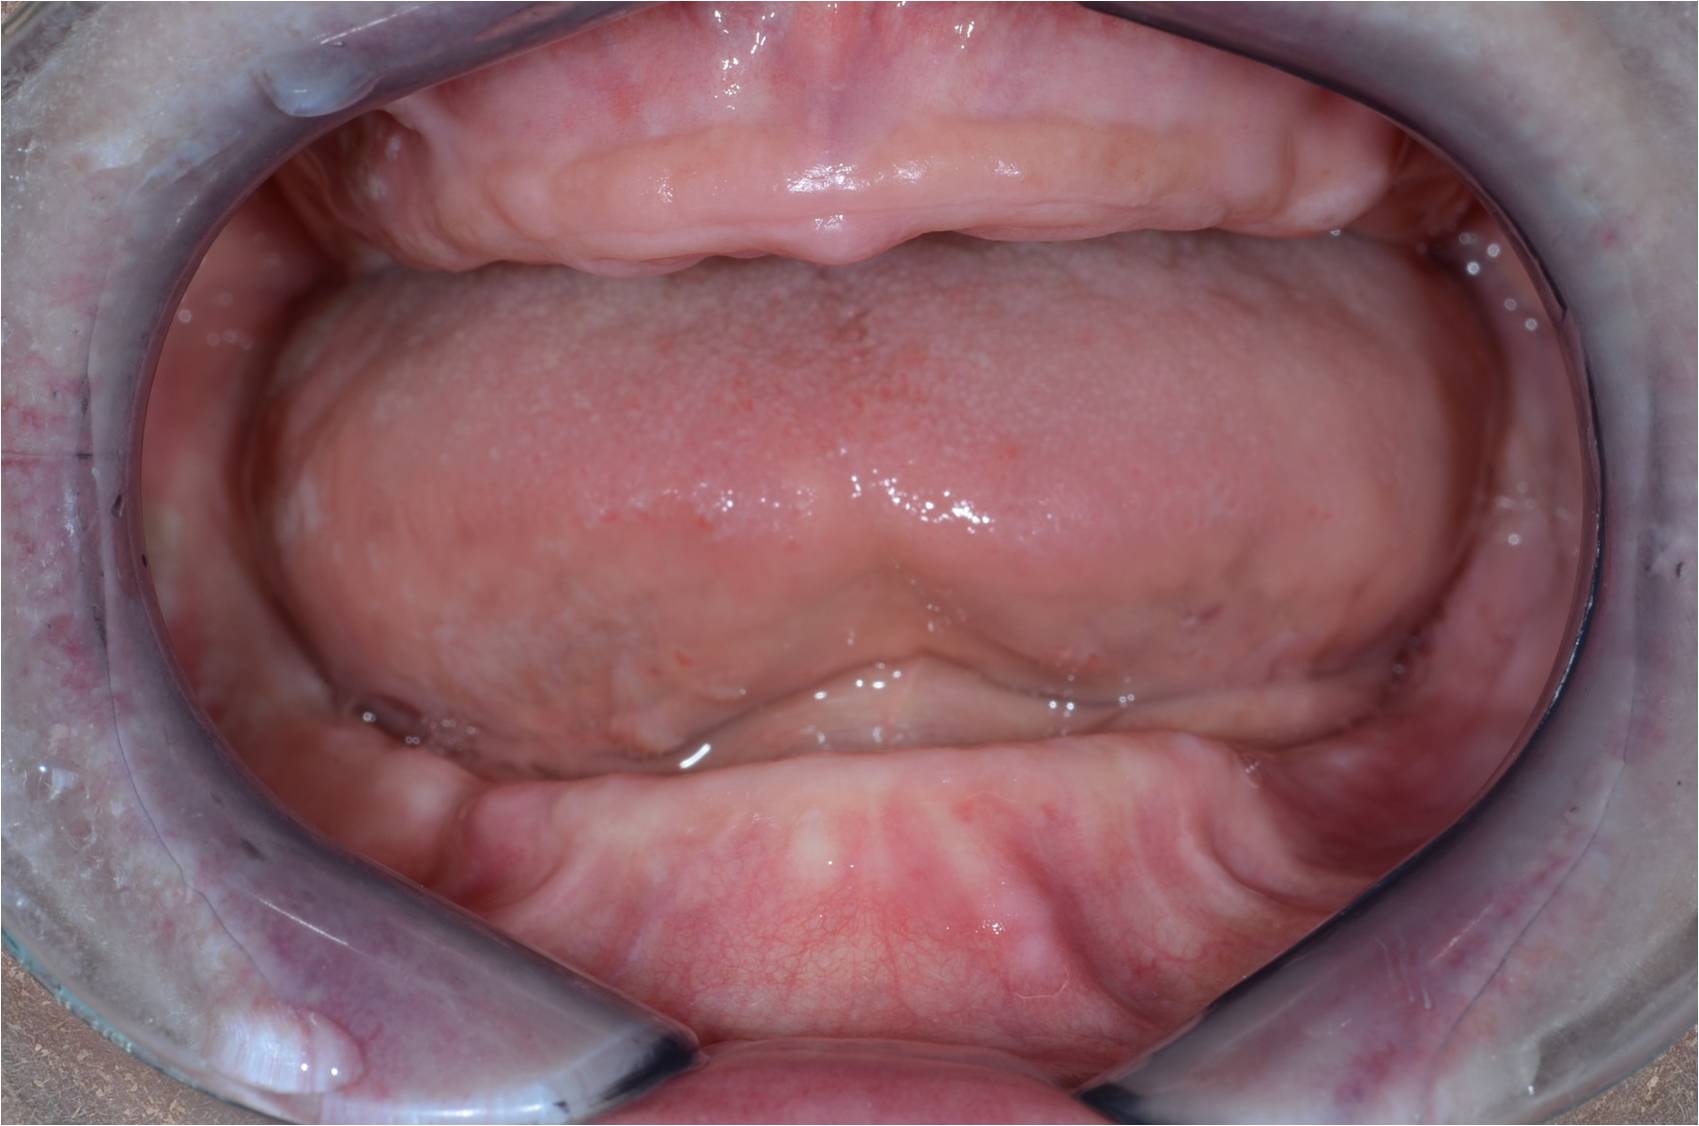

Initial consultations evaluate patients existing teeth and bone.

Panoramic x-ray showing missing teeth in both arches